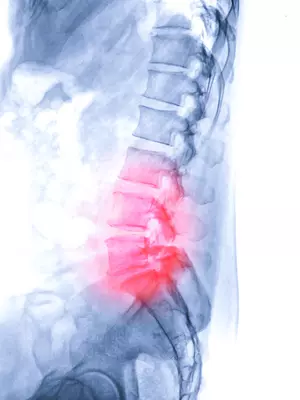

허리 협착증은 척추관이나 추간공이 좁아져 척추 신경이 압박되는 질환입니다. 다리 통증, 무감각, 저림, 근력 약화 등의 증상을 유발하며, 심각한 경우 장기적인 기능 장애를 초래할 수도 있습니다. 허리 협착증 치료에는 신경성형술과 풍선확장술 두 가지 주요 시술 방법이 있습니다. 두 시술 모두 척추관이나 추간공을 확장하여 척추 신경 압박을 완화하는 방식이지만, 시술 방법, 효과, 장점, 단점 등에서 차이점이 있습니다.